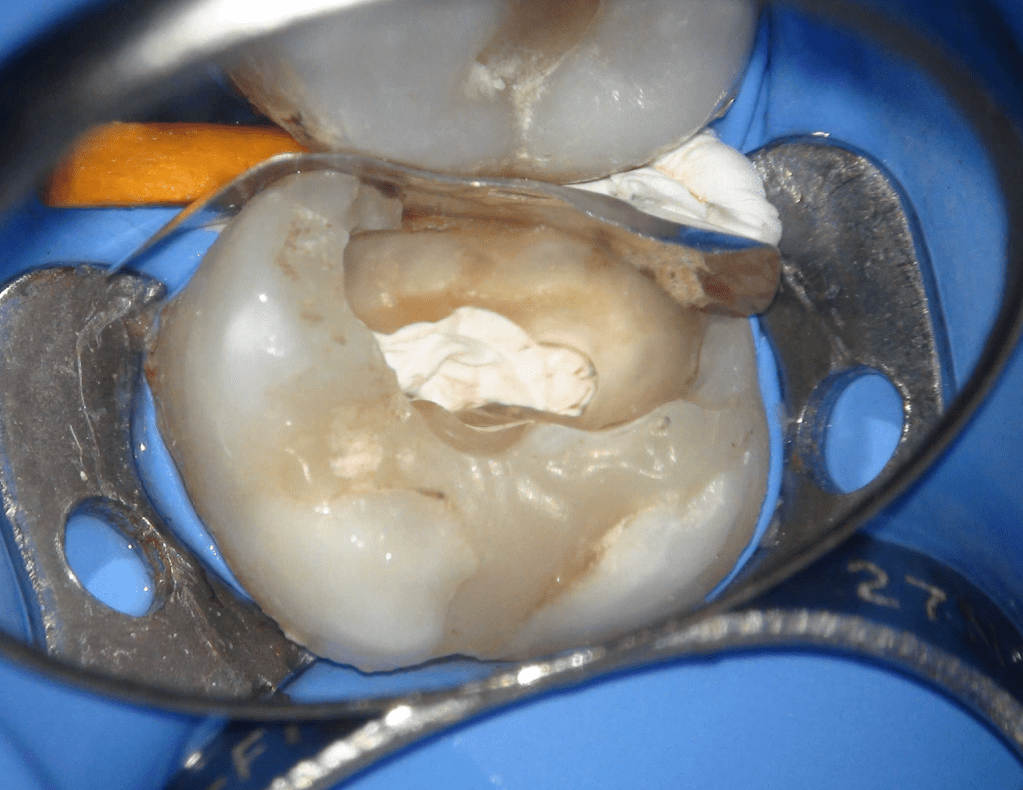

Reconstrucción preendodóntica

Reco preendo + 4 conductos molar superior